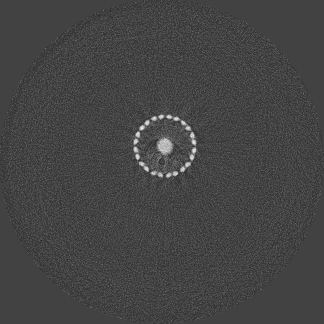

Photon-counting detectors have been successfully employed in preclinical applications. Using spectral imaging, a novel approach towards minimising beam hardening effects is proposed. To the best of our knowledge, beam hardening and metal artefact reduction using spectral imaging has not been reported. Unlike numerical techniques, the work described in this paper aims at minimising metal artefacts in the acquisition stage, by capturing high energy quanta that exhibit less beam hardening effects. The Medipix ASIC allows simultaneous data acquisition from discrete user-defined energy ranges. The ASIC was designed to count photon events and categorise them based on energy thresholds determined by the user. This feature enables the capture of spectral signatures for multiple materials which can be used for material discrimination. The number of counts for discrete energy bands can be obtained by subtracting data from two counters. This is essentially done as a pre-processing step prior to flat-field normalization and reconstruction. The raw data from a counter has an energy range between [, kVp], where is the corresponding user-defined threshold and kVp is the x-ray tube potential used. Since the count information is acquired simultaneously in a single exposure, the noise in a particular energy range is local Poisson noise due to quantum fluctuations. Reduction in streak artefacts using spectral imaging of a scaffold sample is shown in figure 1. Wide energy acquisition shows severe streaks while narrow high energy range exhibits reduced artefacts. Also, spatial improvements corresponding to the metal region can be noticed in the narrow energy band while the wide energy reconstruction shows a blooming effect.

Figure 5 illustrates a single slice spectral reconstruction of the Ti scaffold. Varying levels of streak artefacts can be seen across the spectral reconstructions. The spectral reconstructions for the energy ranges 35 to 80 keV, 55 to 80 keV, and 62 to 80 keV shown in figure 5, exhibit reduced streak artefacts. A region-of-interest (ROI) analysis was performed in the immediate vicinity of the metal region where the streaks are more pronounced. Average attenuation coefficent of air close to zero conveys less regional noise/artefacts. The regional average attenuation coefficient () of the non-metal (air) region in 55 to 80 keV reconstruction (figure 5c) shows reduced artefacts. Even though minor streaks and statistical noise appear in figure 5d due to photon limitation, the artefacts are less pronounced in comparison to the wide energy acquisition in figure 5a.